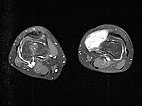

Axial T2-weighted MRI shows a hyperintense, homogeneous mass in the area of the swelling. Morphology very compatible with a venous malformation. Strikingly, some smaller central flow voids suggestive of arteries in the lesion.

The axial T2-weighted, fat-saturated MRI slightly more cranial again depicts typical signs of a venous malformation with severe hyperintensity of the lesion.

The completely occluded venous malformation, which in this case had contained multiple arteriovenous fistulas, was successfully resected after successful embolization and sclerotherapy with complete occlusion. Axial T2-weighted MRI demonstrates the completeness of the resection without a remaining lesion.